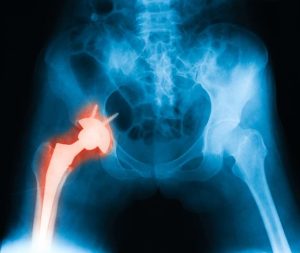

- When there is damage to the bone – X-rays alongside other imaging tests can be used to check if osteoarthritis or any other medical condition has taken a toll on the patient’s joints.